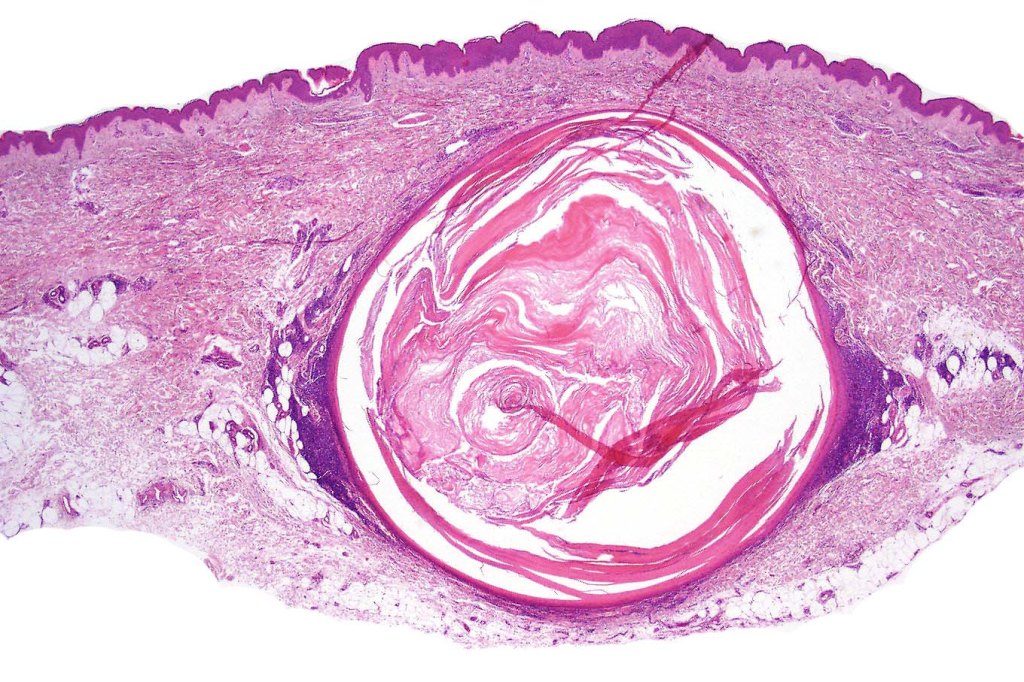

Histological features

•Epidermal involvement often absent

•Follicular infiltration by atypical lymphocytes & Sézary cells

•+/- mucinosis

•+/- basaloid follicular hyperplasia